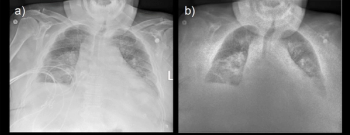

The use of a portable dual-energy X-ray detector in the ICU at one community hospital reportedly facilitated a 37.5 percent decrease in chest CT exams in comparison to the previous three months, according to research presented at the American Society of Emergency Radiology (ASER) meeting in Washington, D.C.